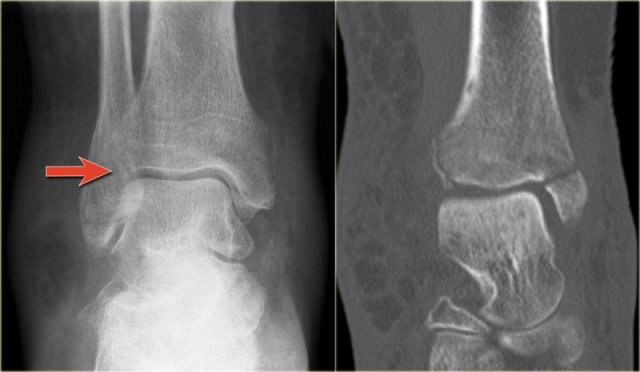

Here we have images of an extremely difficult case.

This woman had a distortion of the ankle and had pain on both medial and lateral side.

She was referred to the radiology department by her general practitioner.

The technician made the standard AP-, Mortise- and lateral view and showed them to the radiologist, who was a little bit puzzled.

First study the images and then continue reading.

The findings are:

• Soft tissue swelling both medial and lateral (red arrows).

Especially the medial swelling should make you consider a pronation exorotation injury (Weber C).

• Lucent line on Mortise view (black arrow) and lateral view. This should make you consider a tertius fracture.

The radiologist decided first to order a CT to find out if there really was a tertius fracture.

Continue with the CT and be amazed.

It is amazing, that such a large tertius fragment is so difficult to see on the radiographs.

Also notice the soft tissue swelling on the medial side indicating rupture of the medial collateral ligaments (arrow).

Medial soft tissue swelling and a tertius fracture are both indications of a Weber C or Pronation Exorotation injury.

Since there is no fibula fracture seen on the x-rays of the ankle, there must be a high fibular fracture.